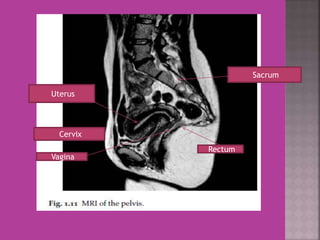

Uterus

Cervix

Vagina

Rectum

Sacrum

Uterus Cervix Vagina Rectum Sacrum